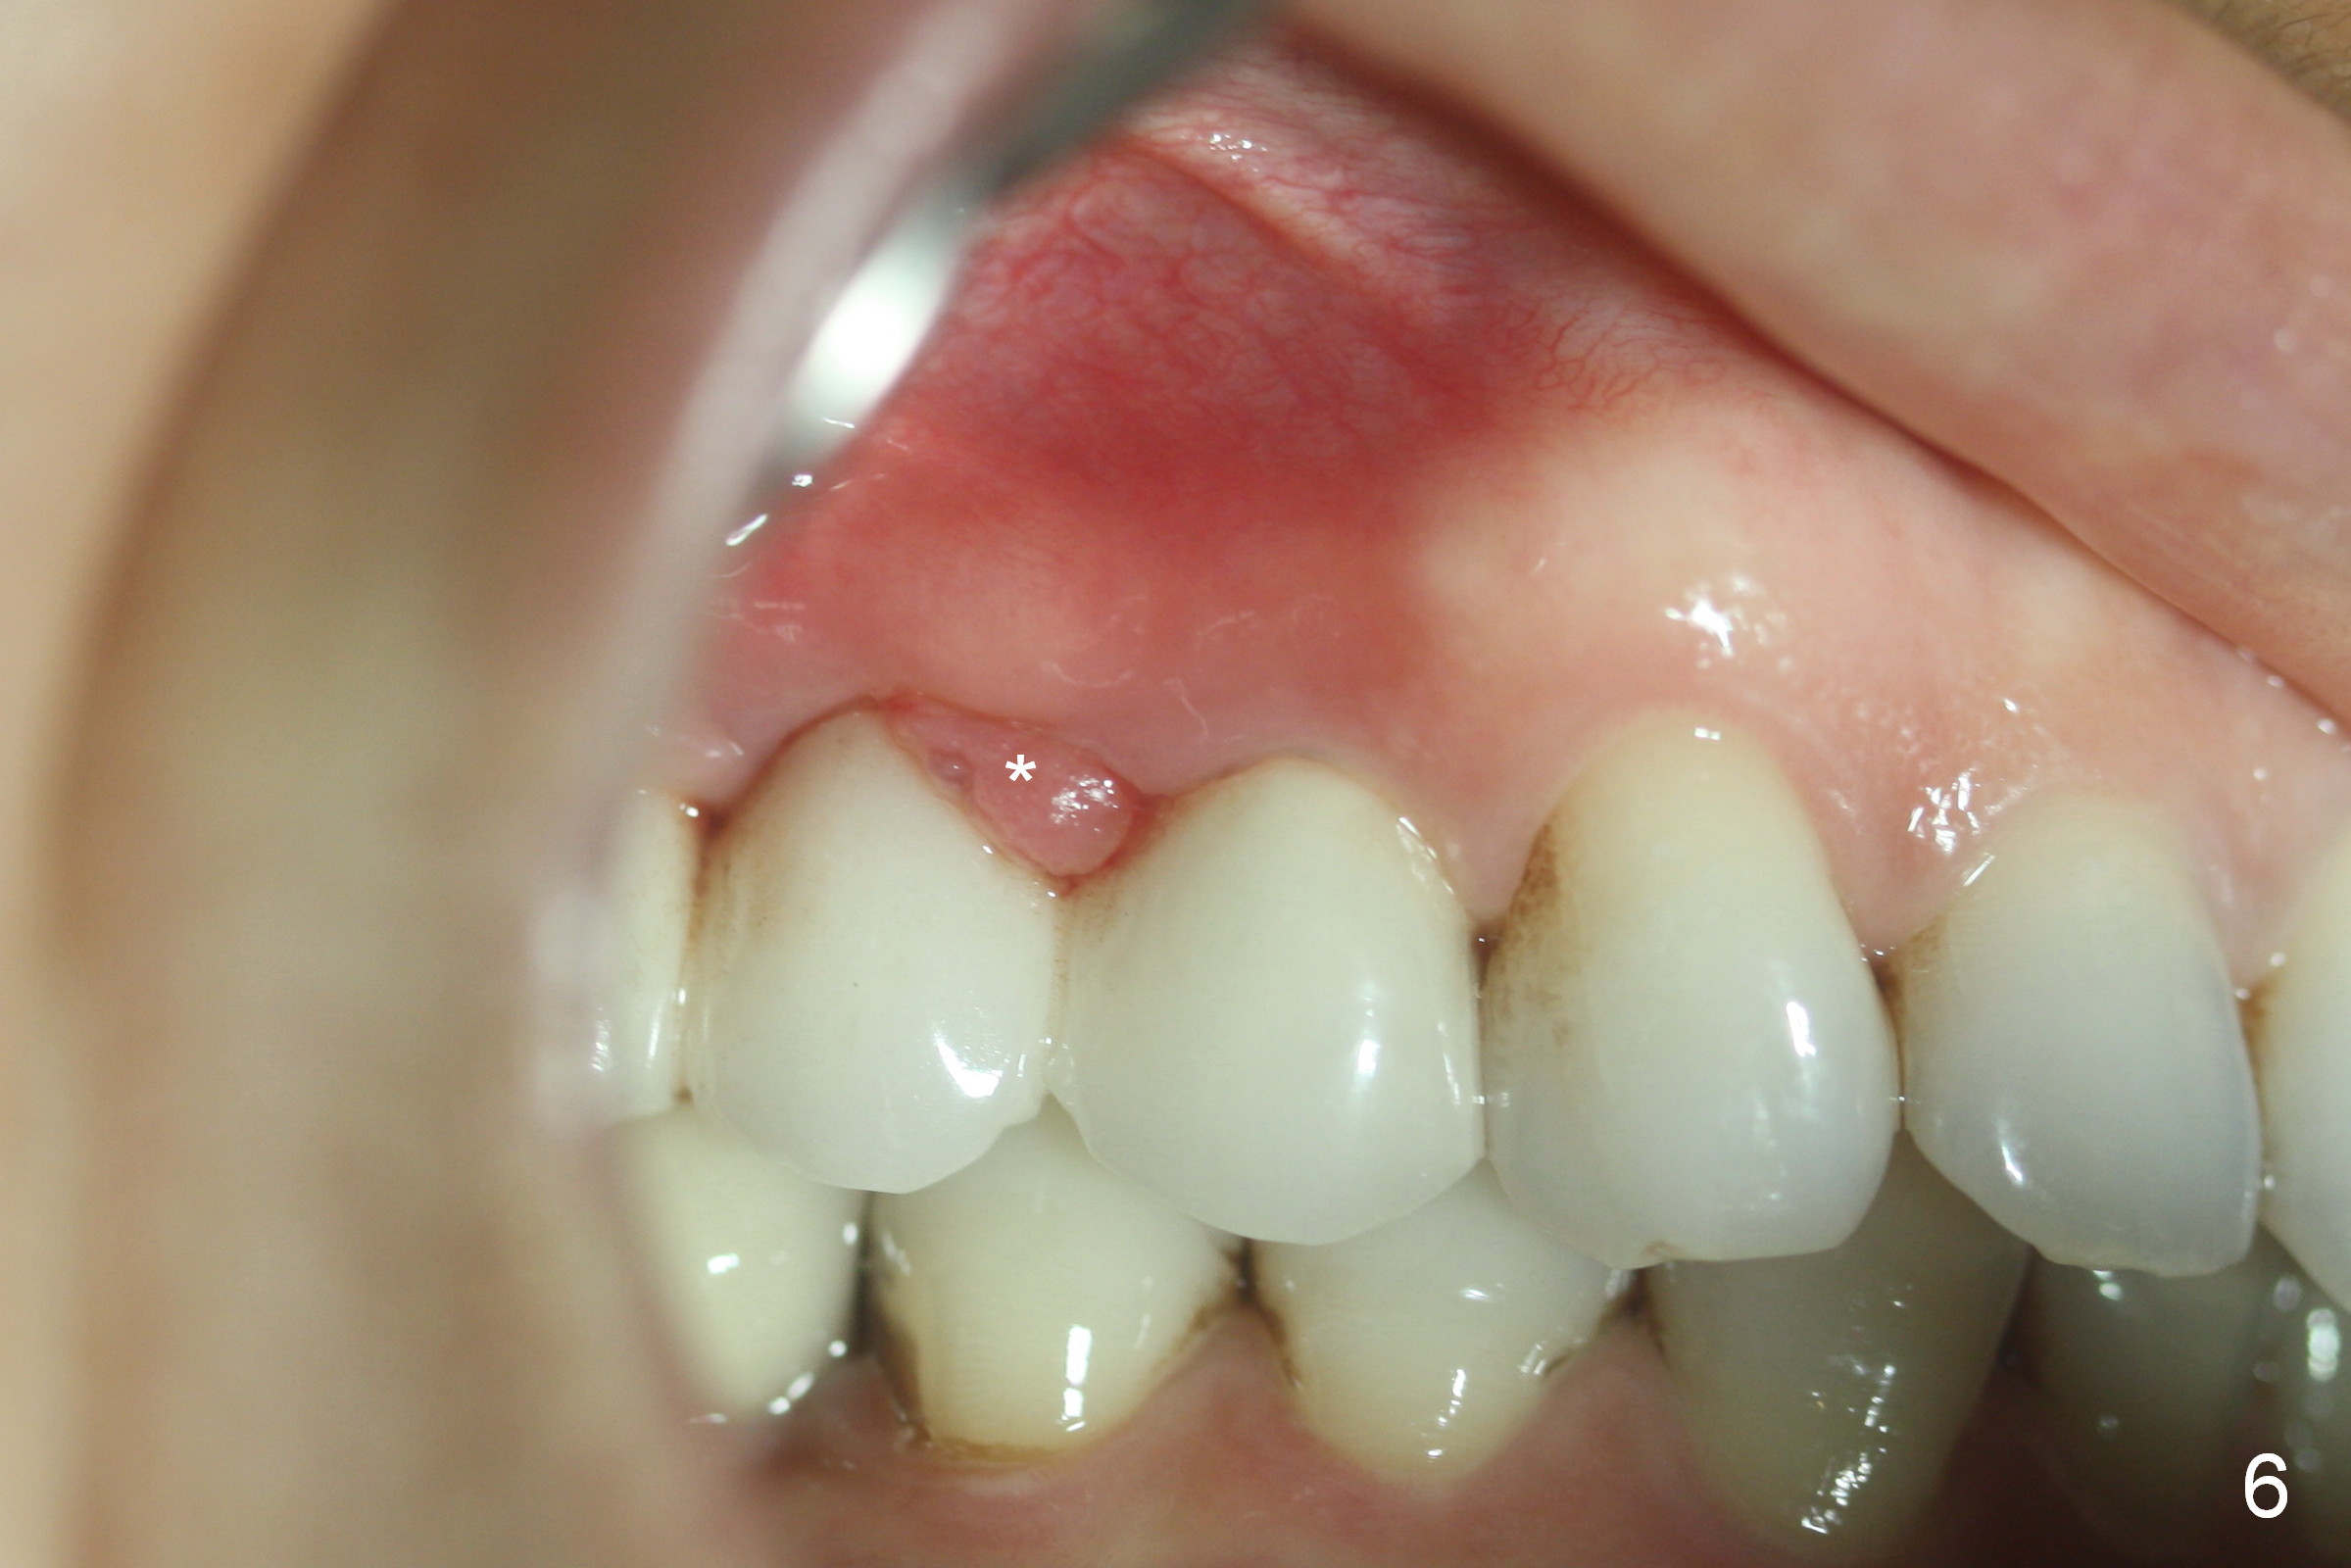

Ms. Li, a 34-year-old lady, had the upper right fixed partial denture made by an unlicensed dentist in California 10 years ago (Fig.1: #3-5). The gingival margin palatal to the retainers is erythematous (Fig.1 arrows). The patient's chief complaint is gum bleeding. The retainer at #3 is over-contoured buccopalatally (Fig.1, as compared to #14 in Fig.2), while the one at #5 is over-contoured buccopalatally and mesiodistally (compare to #12 in Fig.2). Panoramic X-ray (Fig.3), bitewing (Fig.4) and periapical film (Fig.5) all confirm that the bridge is over-contoured and that the retainers #3 and 5 have open margin (Fig.4 arrowheads). To improve oral hygiene and save the abutment teeth #3 and 5, it is in the patient's best interest to remove the bridge, place an implant at #4 and fabricate single-unit crowns at #3 and 5. Three to four months later, pyogenic granuloma develops between #4 and 5 (Fig.6 *) with generalized gingival erythema apically. The pontic at #4 and the retainer at #5 are to be removed first. An implant will be placed at #4 (Fig.7) with conjoined provisional at #4 and 5. The initial depth of osteotomy is 13 mm with Sinus Master Kit.